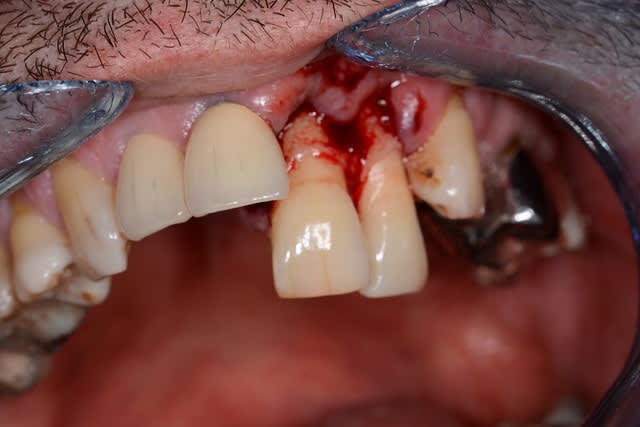

rixe routière